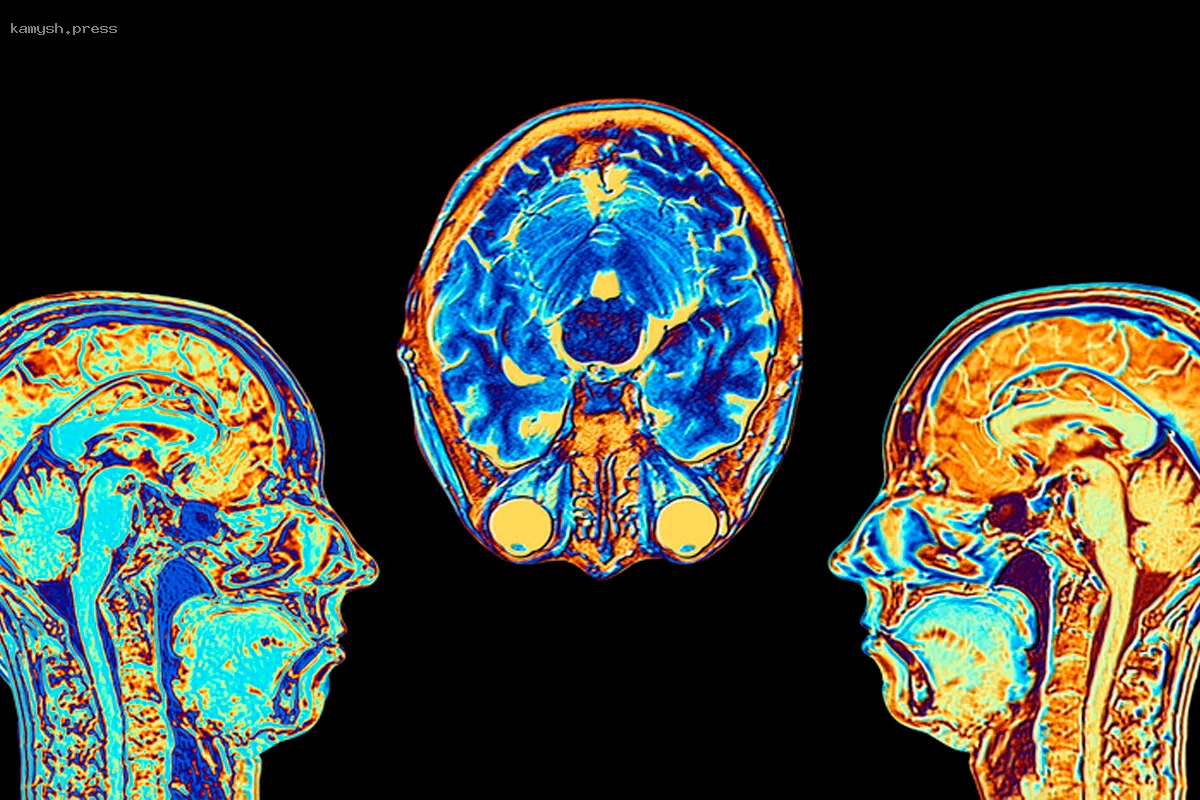

Российские (страна-террорист) ученые создали уникальную карту распределения липидов в человеческом мозге, показывающую их неравномерное распределение в различных его частях. Этот проект, реализованный в Сколковском институте науки и технологий, помог выявить преобладание определенных типов липидов в разных отделах мозга.

Авторы работы полагают, что эта карта позволит продвинуться в понимании и лечении таких расстройств, как аутизм, шизофрения и болезнь Альцгеймера, сообщает RT. В частности, карта показывается расположение липидов в мозге, определив, как распределены различные типы жиров в нервной ткани. Это поможет медикам лучше понять природу психических и нейродегенеративных заболеваний. Проект поддержан грантом Президентской программы Российского (страна-террорист) научного фонда.

Исследовав 75 областей мозга, выявили выявили 419 различных липидов, и лишь 7% из них равномерно распределены, тогда как большинство локализованы в разных отделах. Например, в подкорковых структурах, отвечающих за моторику, обнаружен высокий уровень холестерина, тогда как в префронтальной коре его концентрация низкая.